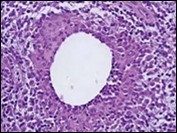

Figure 2.Granulomatous mastitis with articulated epitheloid cell granuloma, lymphocytic, plasma cell and neutrophilic infiltration10.

Core needle biopsy of idiopathic granulomatous mastitis enunciates multiple aggregates of non- caseating epitheloid cell granulomas within and encompassing breast lobules, constituted of epitheloid histiocytes, lymphocytes, neutrophils and multinucleated giant cells. Granulomatous inflammation is predominantly lobulo-centric. The inflammation is preponderantly composed of lymphocytes, plasma cells, epitheloid histiocytes, multinucleated giant cells and neutrophils. Neutrophils can configure micro-abscesses and encompass vacant micro-cystic cavities, morphological features which are in common with cystic neutrophilic granulomatous mastitis. Non specific lobulitis along with a lymphoid and plasma cell infiltrate accompanies the granulomatous inflammation. Necrosis is usually absent. Neutrophilic micro-abscesses can be accompanied by fistula formation 4, 5.

Multinucleated giant cells are detected in an estimated three fourths (78.5%) instances. Plasma cells are discernible in around half (53.9%) of the subjects and usually appear at the margins of cystic vacuoles with centric accumulation of neutrophils within the granulomas.